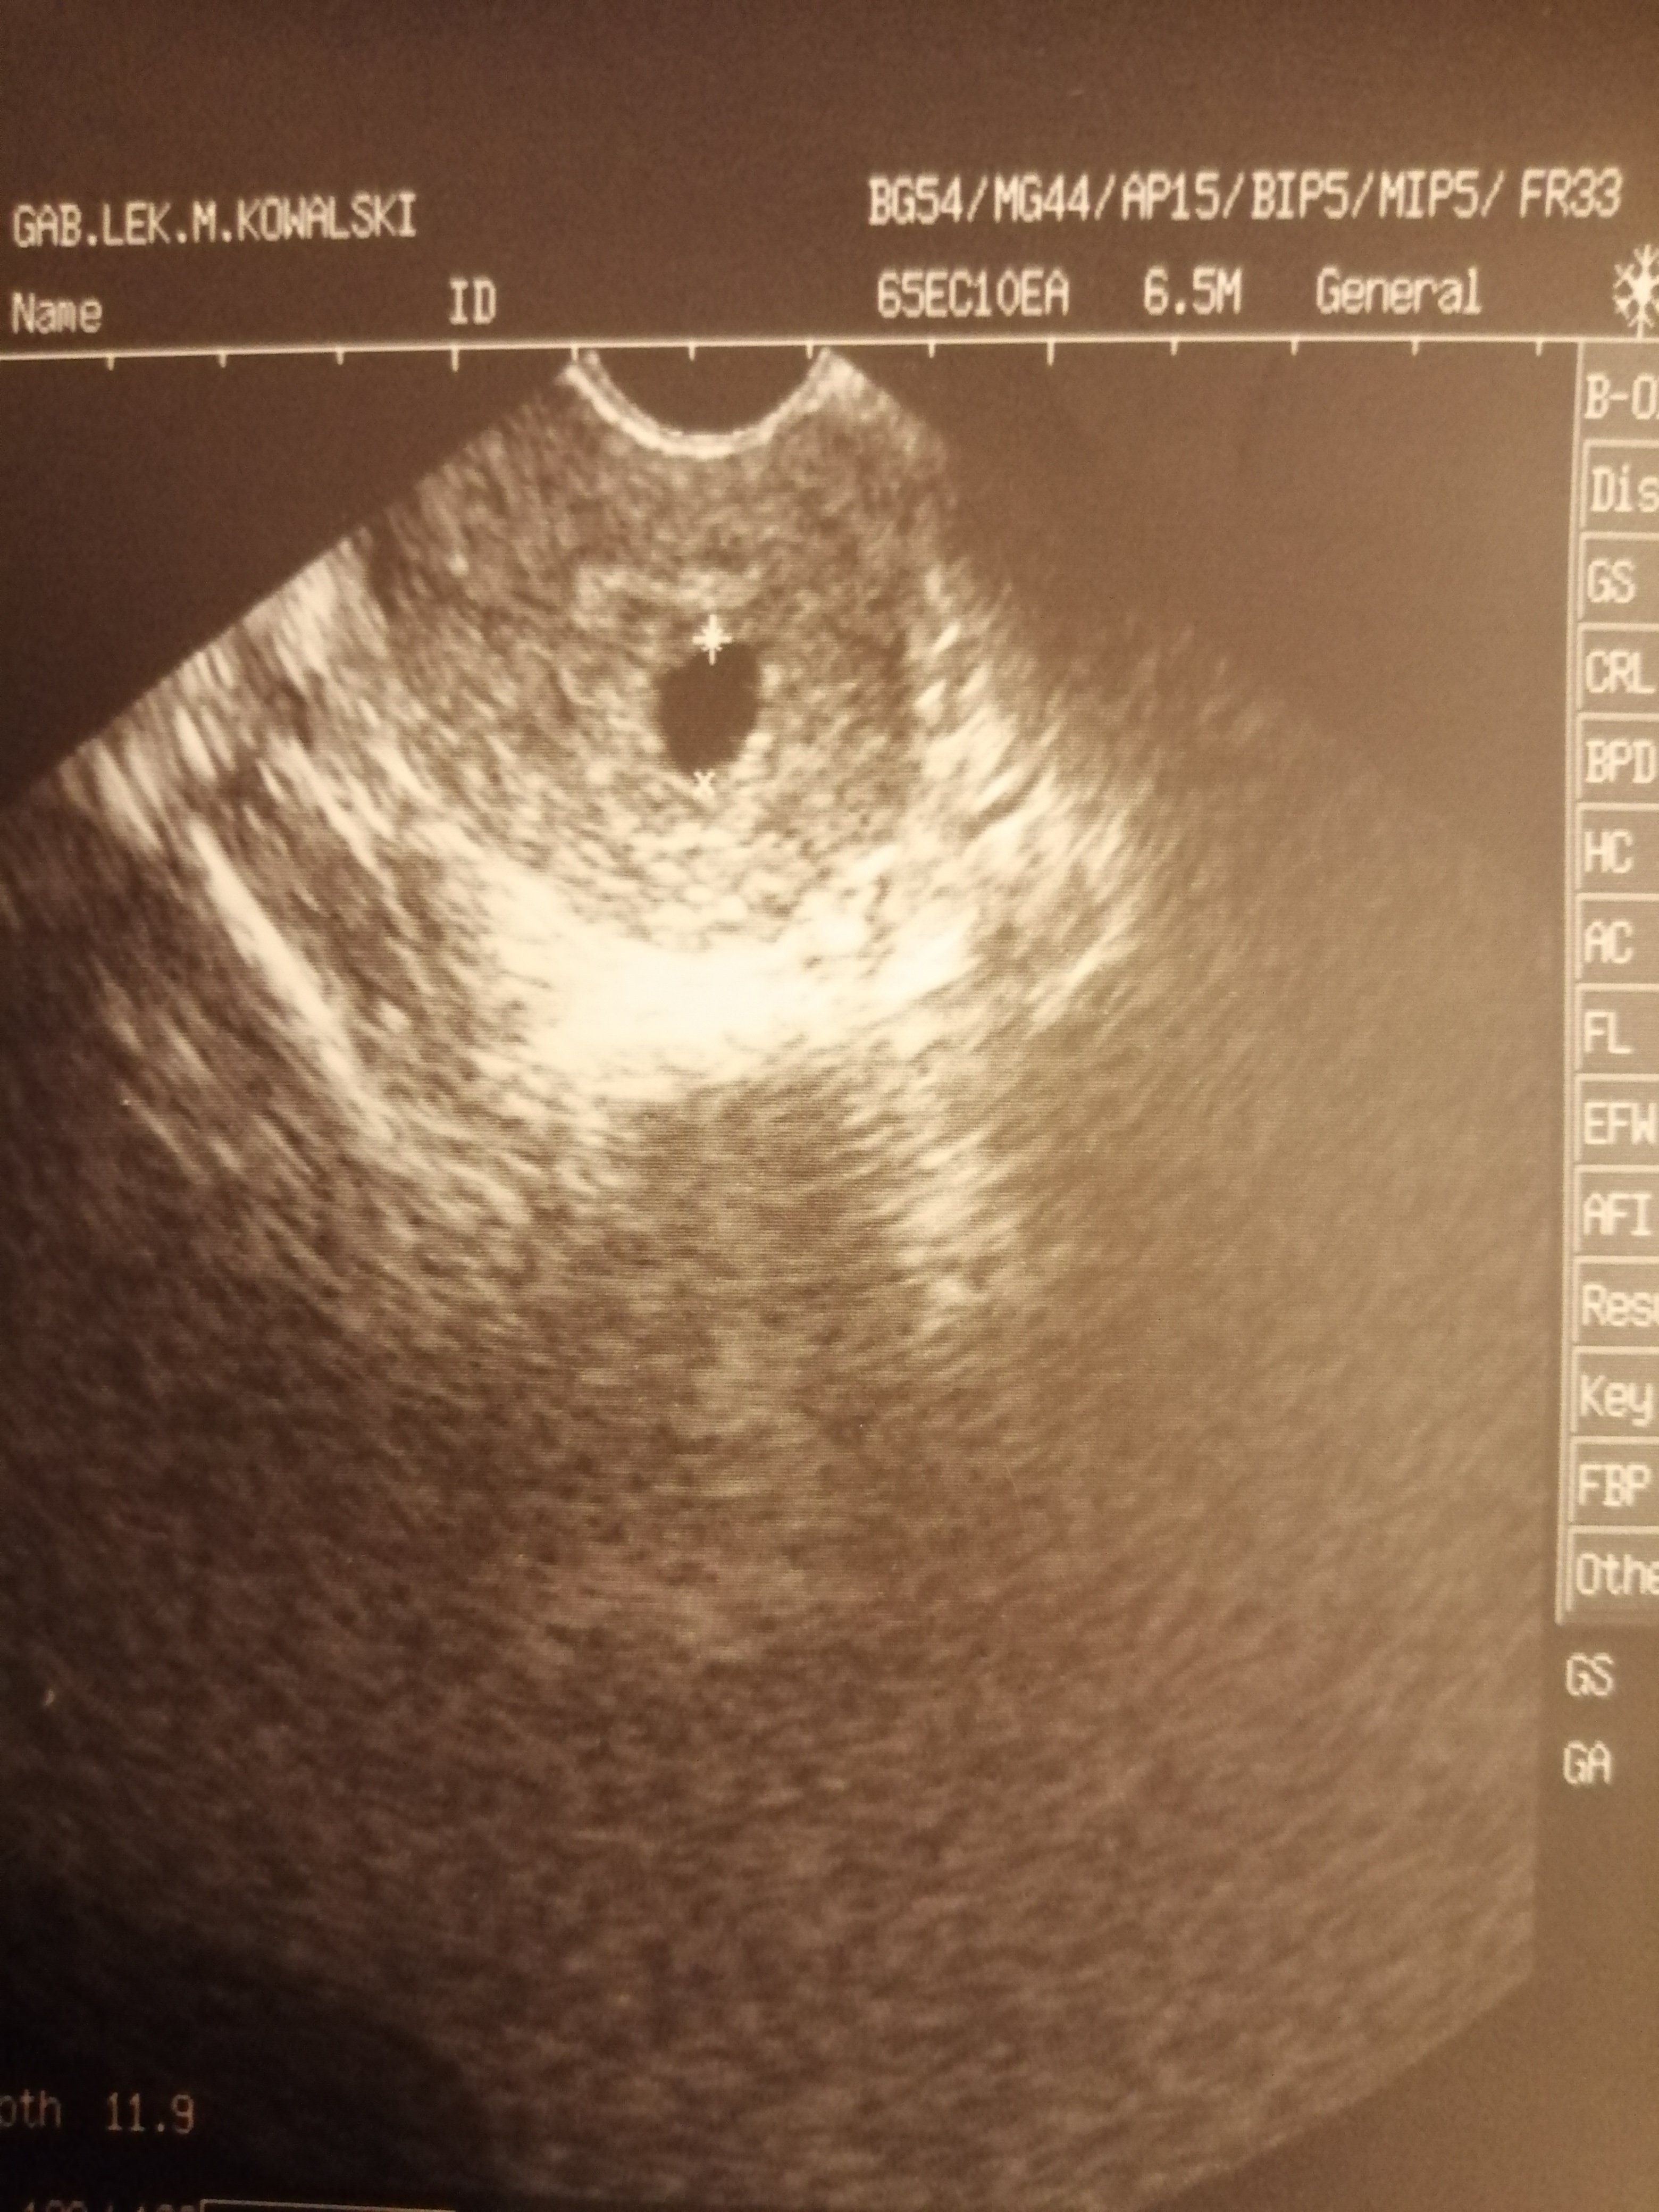

11 września zrobiłam test i dwie kreski się pojawiły. Teraz we wtorek byłam na wizycie u gina i po tym jak mnie potraktował to idzie zwariować, czekam na kolejną wizytę oczywiście do innego lekarza, która ma być 1 października i może coś więcej się wyjaśni. Bo po wizycie usłyszałam, że pęcherzyk ciążowy jest, ale czy coś z tego będzie to nie wiadomo może się utrzyma, a może poleci. Zero delikatności.. Czy wy w ogóle coś widzicie na tym usg. Ja już sobie wkręcam, że może jest pusty pęcherzyk. Itp. Pozdrawiam.

Z moich wyliczeń to taki 7 tydzień. Na usg jest 4 tydzień i 5 dzień.

A cykle mam strasznie nierugalrne. Trwają różnie raz 31,34a nawet 38. Bety nie robiłam.